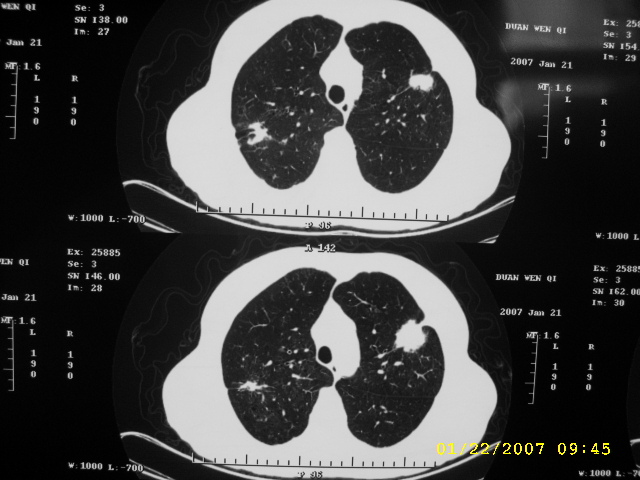

女,75.胸痛。

07.01.21.

明显的不规则形肿块,分叶、短毛刺、胸膜刺激征,血管扭曲征等周围型肺癌的征象明显,应首先考虑周围型肺癌。应与肺多发结核球相鉴别

双侧肺内块状病灶,均见分叶毛刺,左肺见典型胸膜凹陷,双侧双原发癌.

1.双肺上叶及右肺下叶结节,周围散在卫星灶,接近4年的病史,纵隔无肿大淋巴结,考虑结核

2.桶状胸,慢支,肺气肿